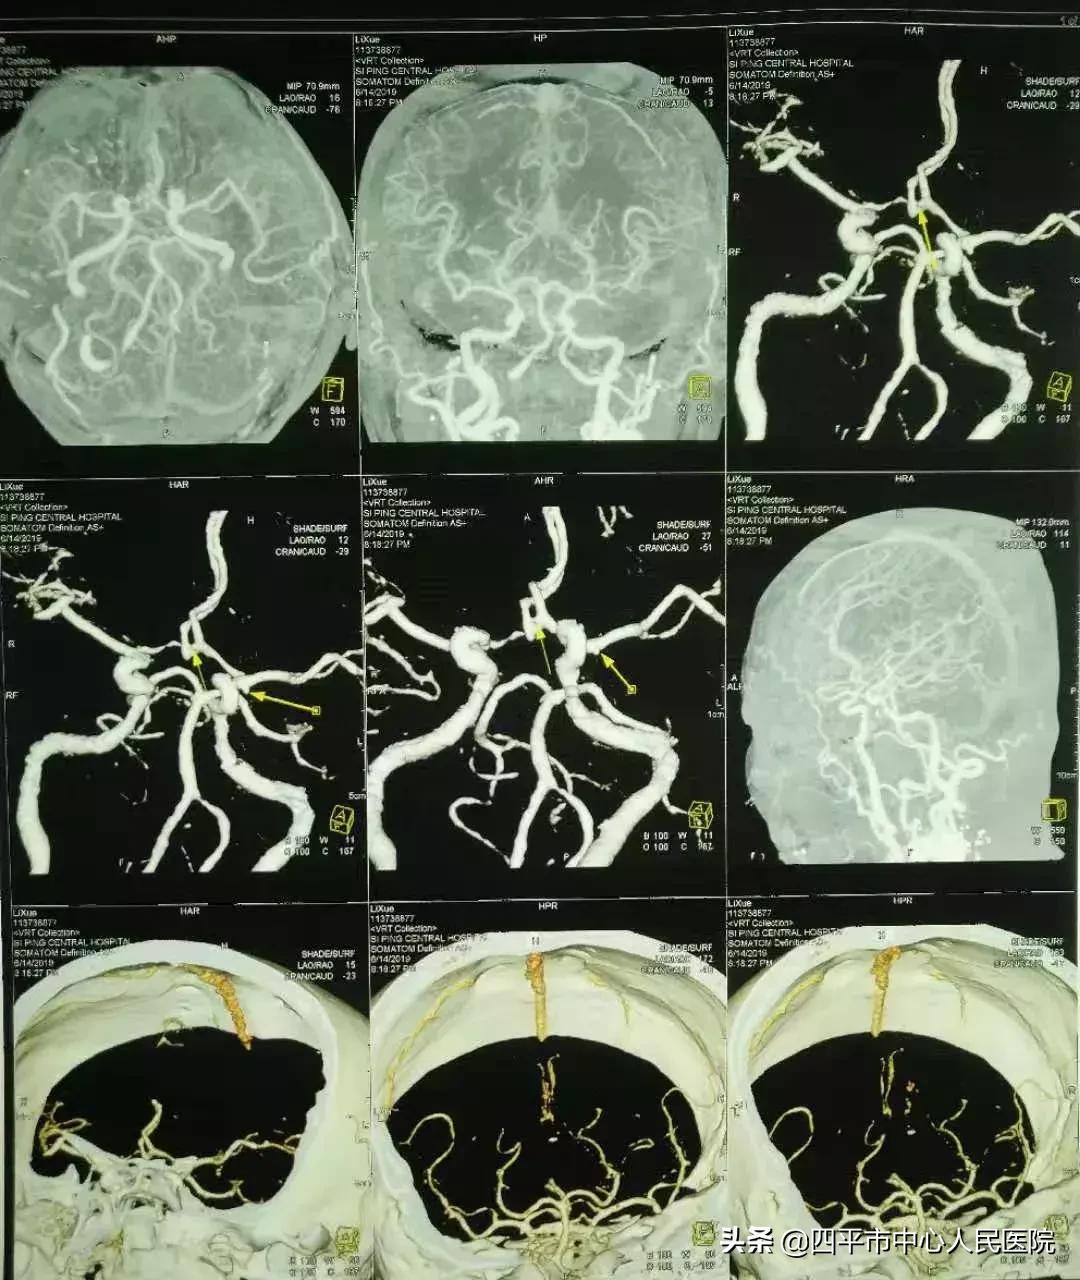

Case1 左侧颈内动脉末端囊状动脉瘤

患者刘XX,缘于入院前2小时无明显诱因在劳动时突发意识不清,从2米高处坠落,既往身体健康,入院头部CT提示蛛网膜下腔出血,李晓东主任阅头部CT片后指示该患者应该是先脑出血而后摔倒,不能除外动脉瘤破裂,入院后完善头部CTA检查,提示1.左侧颈内动脉末端动脉瘤。2.左侧大脑中动脉闭塞。3.双侧颈内动脉颅内段轻度狭窄。4.脑内动脉粥样硬化改变。5.右侧胚胎型大脑后动脉。李晓东主任带领孙庆华急诊全麻下行左侧颈内动脉末端动脉瘤夹闭术,术中注意避免误夹后交通动脉,否则造成的后果是灾难性的,经术中仔细操作,确切夹闭动脉瘤,术中顺利,术后患者病情逐渐好转,出院时神清语明,四肢肌力5级,送来锦旗表示感谢。